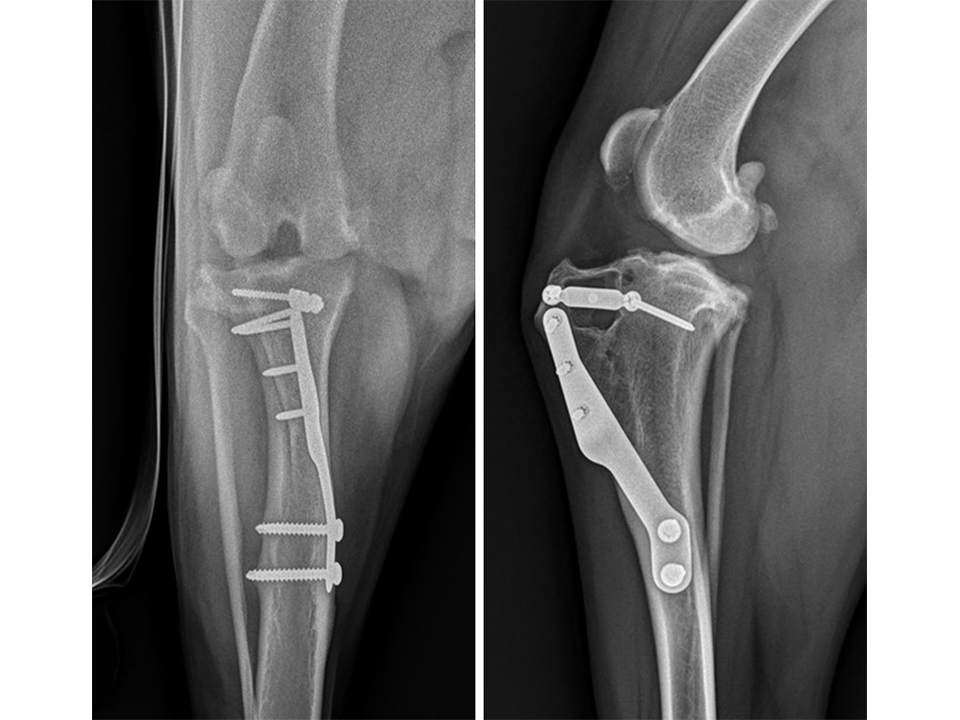

The patient presented again 11 months postoperatively for assessment of right pelvic limb lameness associated with CrCL rupture. At this stage severe right pelvic limb lameness was evident but no lameness of the left pelvic limb was observed. While the right stifle joint was unstable in cranial drawer and CrTT, the left stifle remained stable with no pain response upon palpation over the implants and a normal range of motion of the joint. Radiographs of the previously operated left stifle (Fig 9) revealed no implant-associated complications and healing of the osteotomy. The osteoarthritic changes were static radiographically. TTA was performed on the right tibia at this time using a 13.5 mm wedge and a size 6 plate as had been used on the left previously.